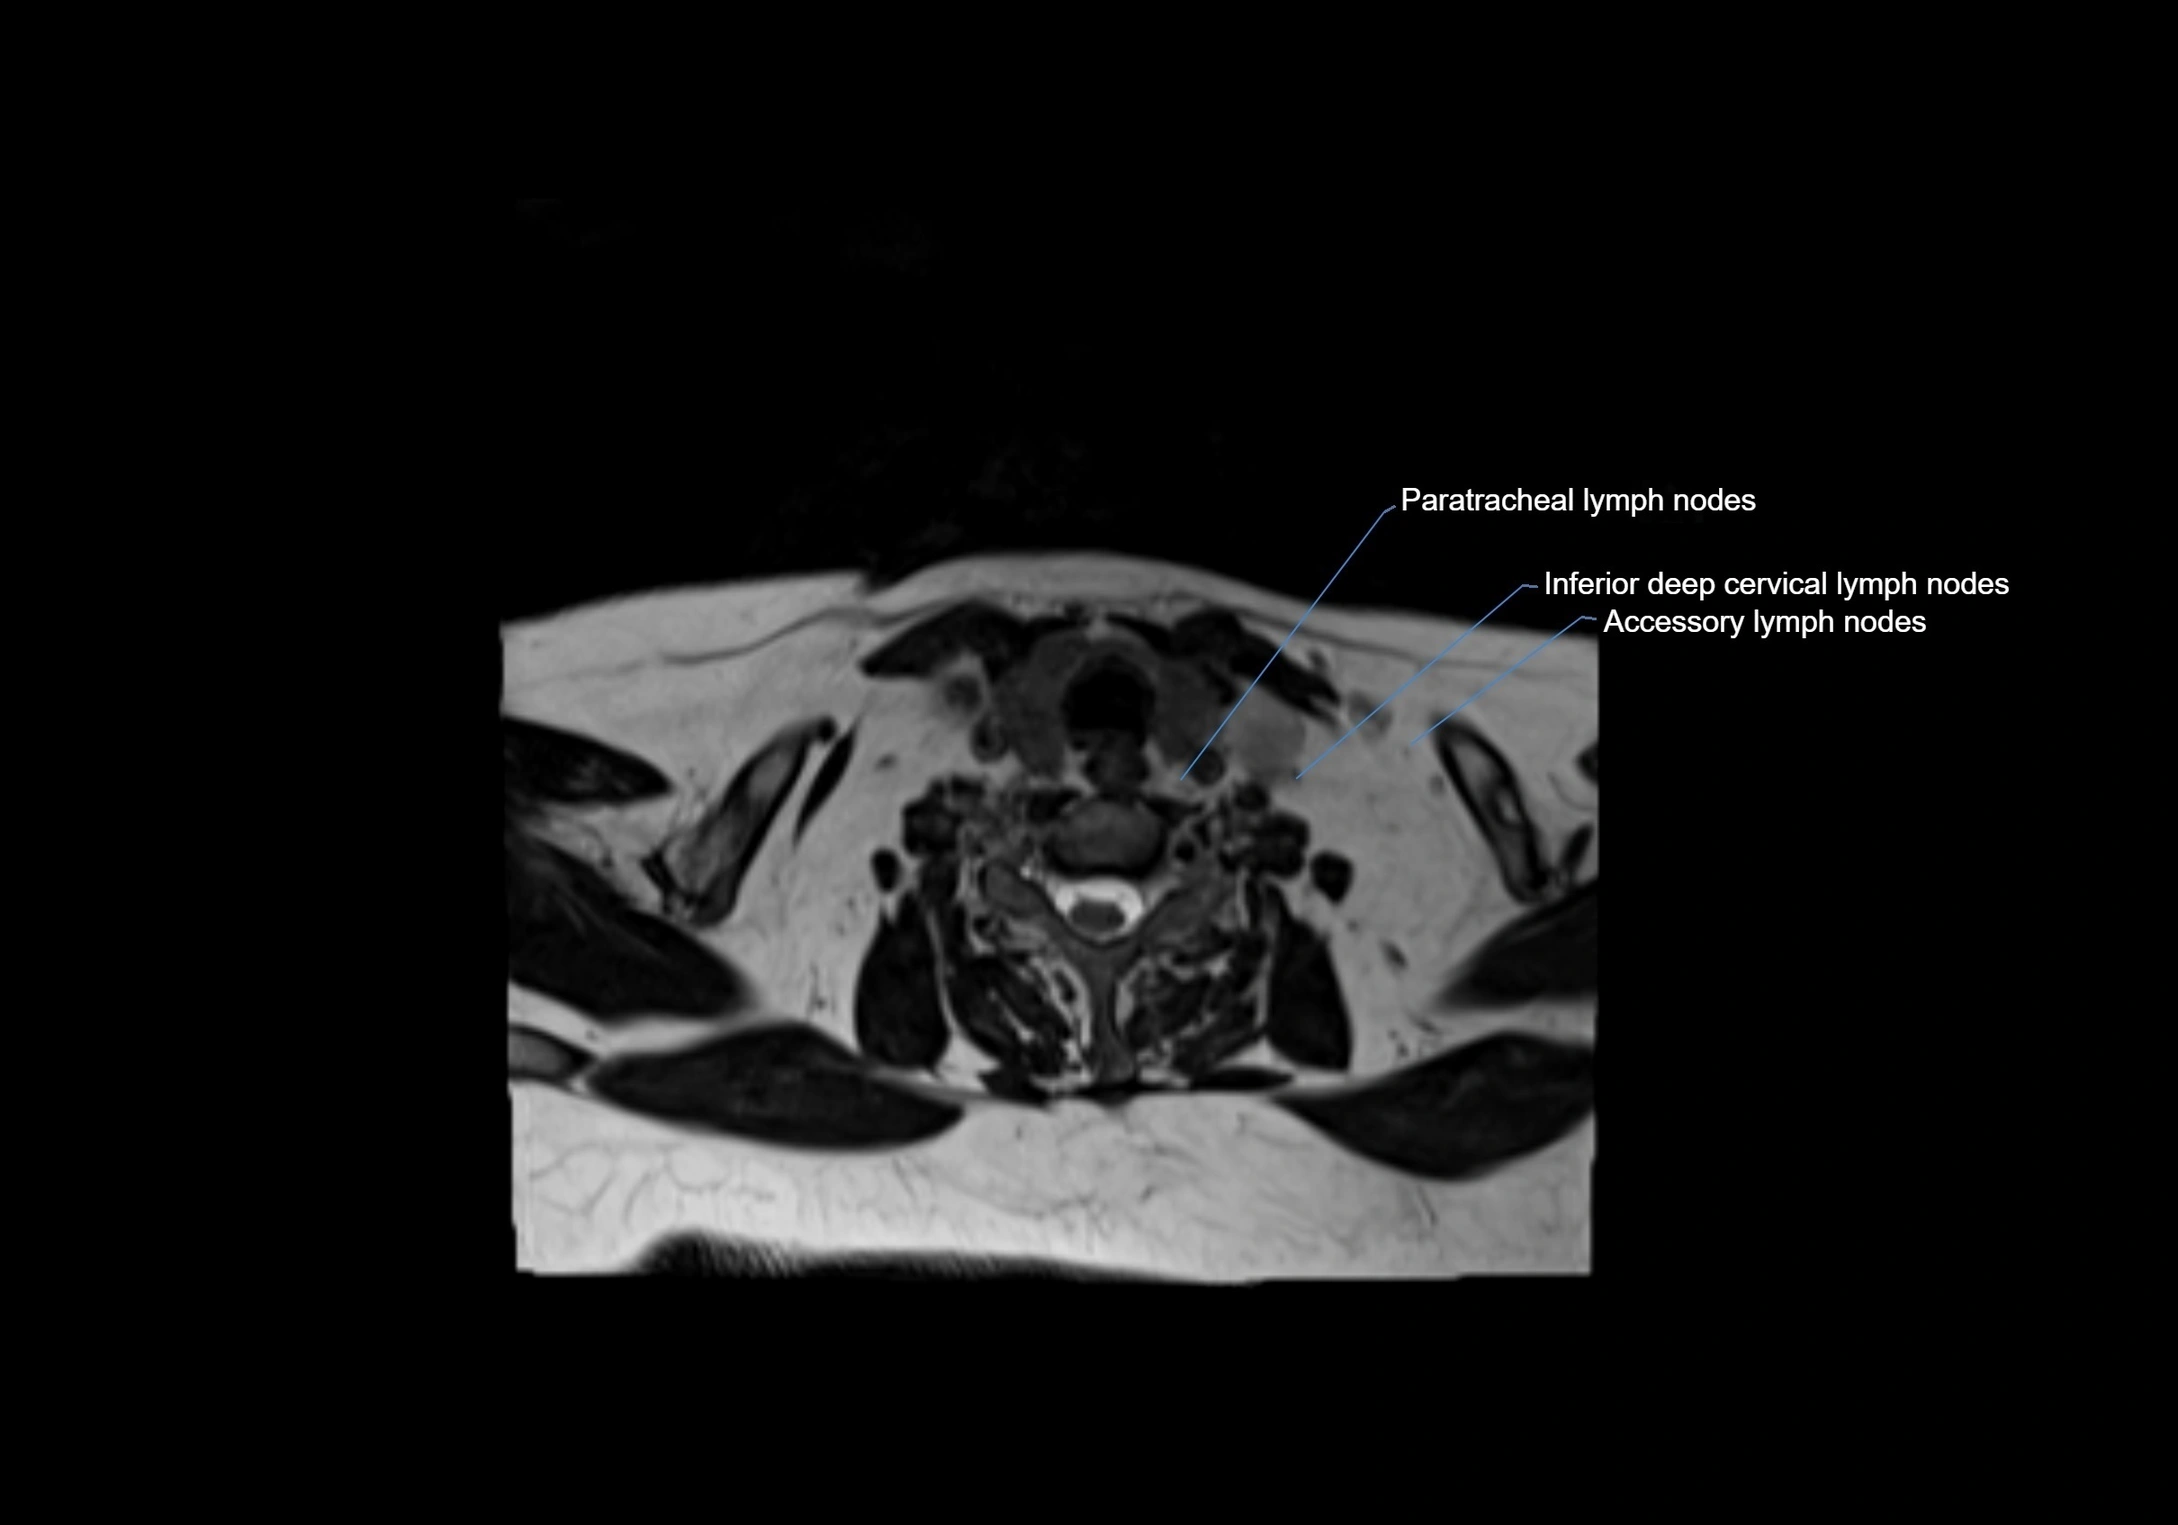

Accessory lymph nodes

Accessory lymph nodes are small, secondary lymph nodes located along the main facial and cervical lymphatic chains, often adjacent to primary lymph nodes, such as preauricular, submandibular, or occipital nodes. They are typically less than 5 mm in diameter, embedded within subcutaneous fat or connective tissue, and may be variable in number and location. These nodes provide additional filtration and immune surveillance for lymph collected from the face, scalp, and neck regions. Accessory lymph nodes are usually non-palpable in healthy individuals but may enlarge in response to infection, inflammation, or metastasis, making them clinically significant.

MRI images

image